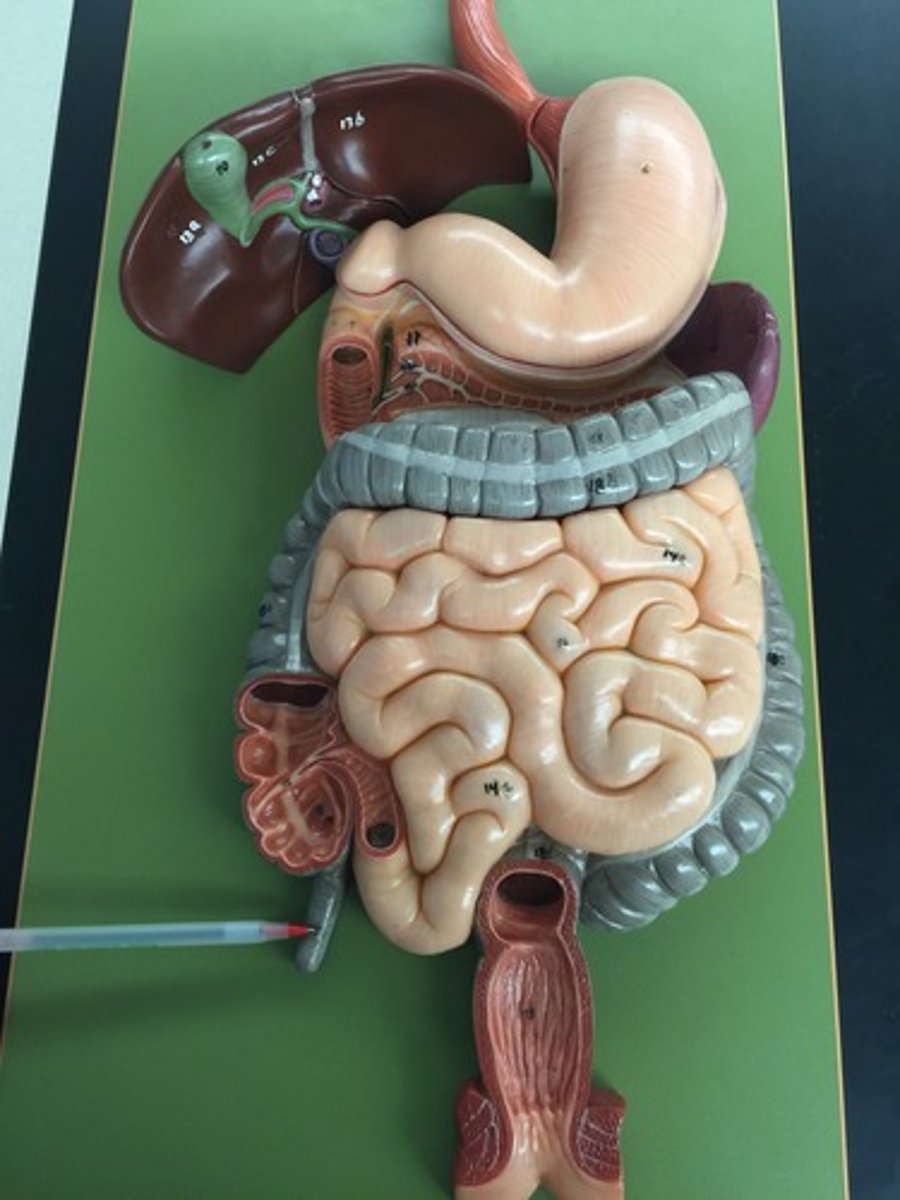

stomach

fundus

cardia

body

lesser curvature

greater curvature

cardiac sphincter / lower esophageal sphincter

pylorus

pyloric sphincter

rugae

lesser omentum

greater omentum

duodenum

duodenum

jejunum

ileum

large intestine

liver

cystic duct

common hepatic duct

Gallbladder

pancreas

pancreatic duct

common bile duct

spleen

hepatopancreatic sphicter / duodenal papilla